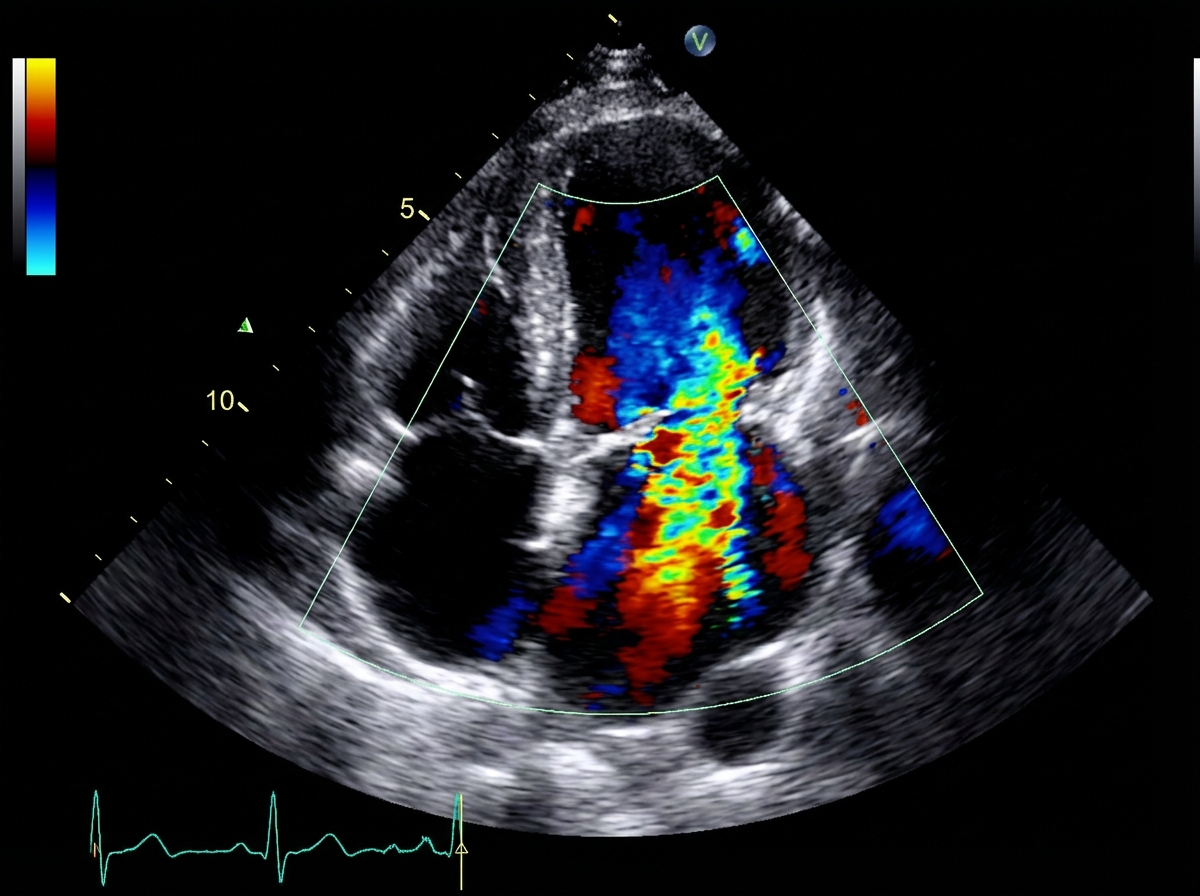

What is the severity of mitral regurgitation (MR)?

Explanation: ***Severe MR*** - **Severe mitral regurgitation** is defined by specific echocardiographic criteria including **regurgitant jet area >40% of left atrial area**, **vena contracta ≥0.7 cm**, and **effective regurgitant orifice area (EROA) ≥0.4 cm²**. - Additional criteria include **regurgitant volume ≥60 mL** and **regurgitant fraction ≥50%** per **ASE/ACC/AHA guidelines**, indicating significant hemodynamic impact. *Profound MR* - **"Profound MR"** is not a recognized clinical grading term in standard echocardiographic classification systems. - Current guidelines use a **four-tier system**: mild, moderate, severe, and sometimes **torrential** for the most extreme cases, but "profound" is not part of established terminology. *Moderate MR* - **Moderate MR** is characterized by **regurgitant jet area 20-40% of left atrial area** and **vena contracta 0.3-0.69 cm**. - **EROA ranges 0.2-0.39 cm²** with **regurgitant volume 30-59 mL** and **regurgitant fraction 30-49%**. *Mild MR* - **Mild MR** shows **regurgitant jet area <20% of left atrial area** and **vena contracta <0.3 cm**. - **EROA is <0.2 cm²** with **regurgitant volume <30 mL** and **regurgitant fraction <30%**, indicating minimal hemodynamic significance.